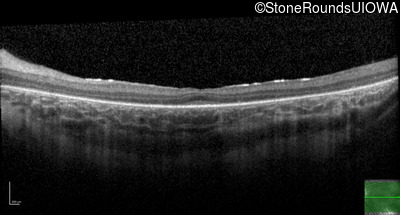

Age at visit: 10 years

OD OS

Age at visit: 11 years

Age at visit: 12 years

Age at visit: 13 years

Age at visit: 14 years

Age at visit: 16 years